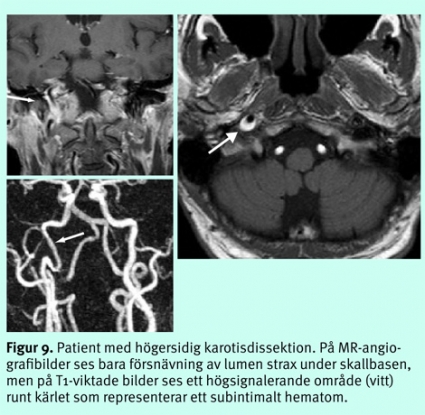

Akuta sjukdomar i halskärlen. Medvetenheten har ökat om att dissektioner i halskärlen är en viktig potentiell orsak till embolisk stroke [11, 12], och om en sådan drabbar arteria vertebralis intradurala segment kan den någon gång vara orsak till subaraknoidalblödning. Bilder bara av lumens grovmorfologi med MR-angiografi eller DT-angiografi är otillräckligt och kan leda till underdiagnostik. MR med T1- och PD-bilder eller analys av kärlväggens tjocklek och attenuering vid DT är viktiga för att avslöja ett subintimalt hematom (Figur 9). Majoriteten av dissektionerna läker inom ett par månader. Relativt stor enighet råder om att en uppföljande undersökning med någon av de dessa modaliteter, eller doppler, cirka 3 månader efter debuten är värdefull för att eventuellt kunna avsluta den antikoagulantiabehandling som är gängse.